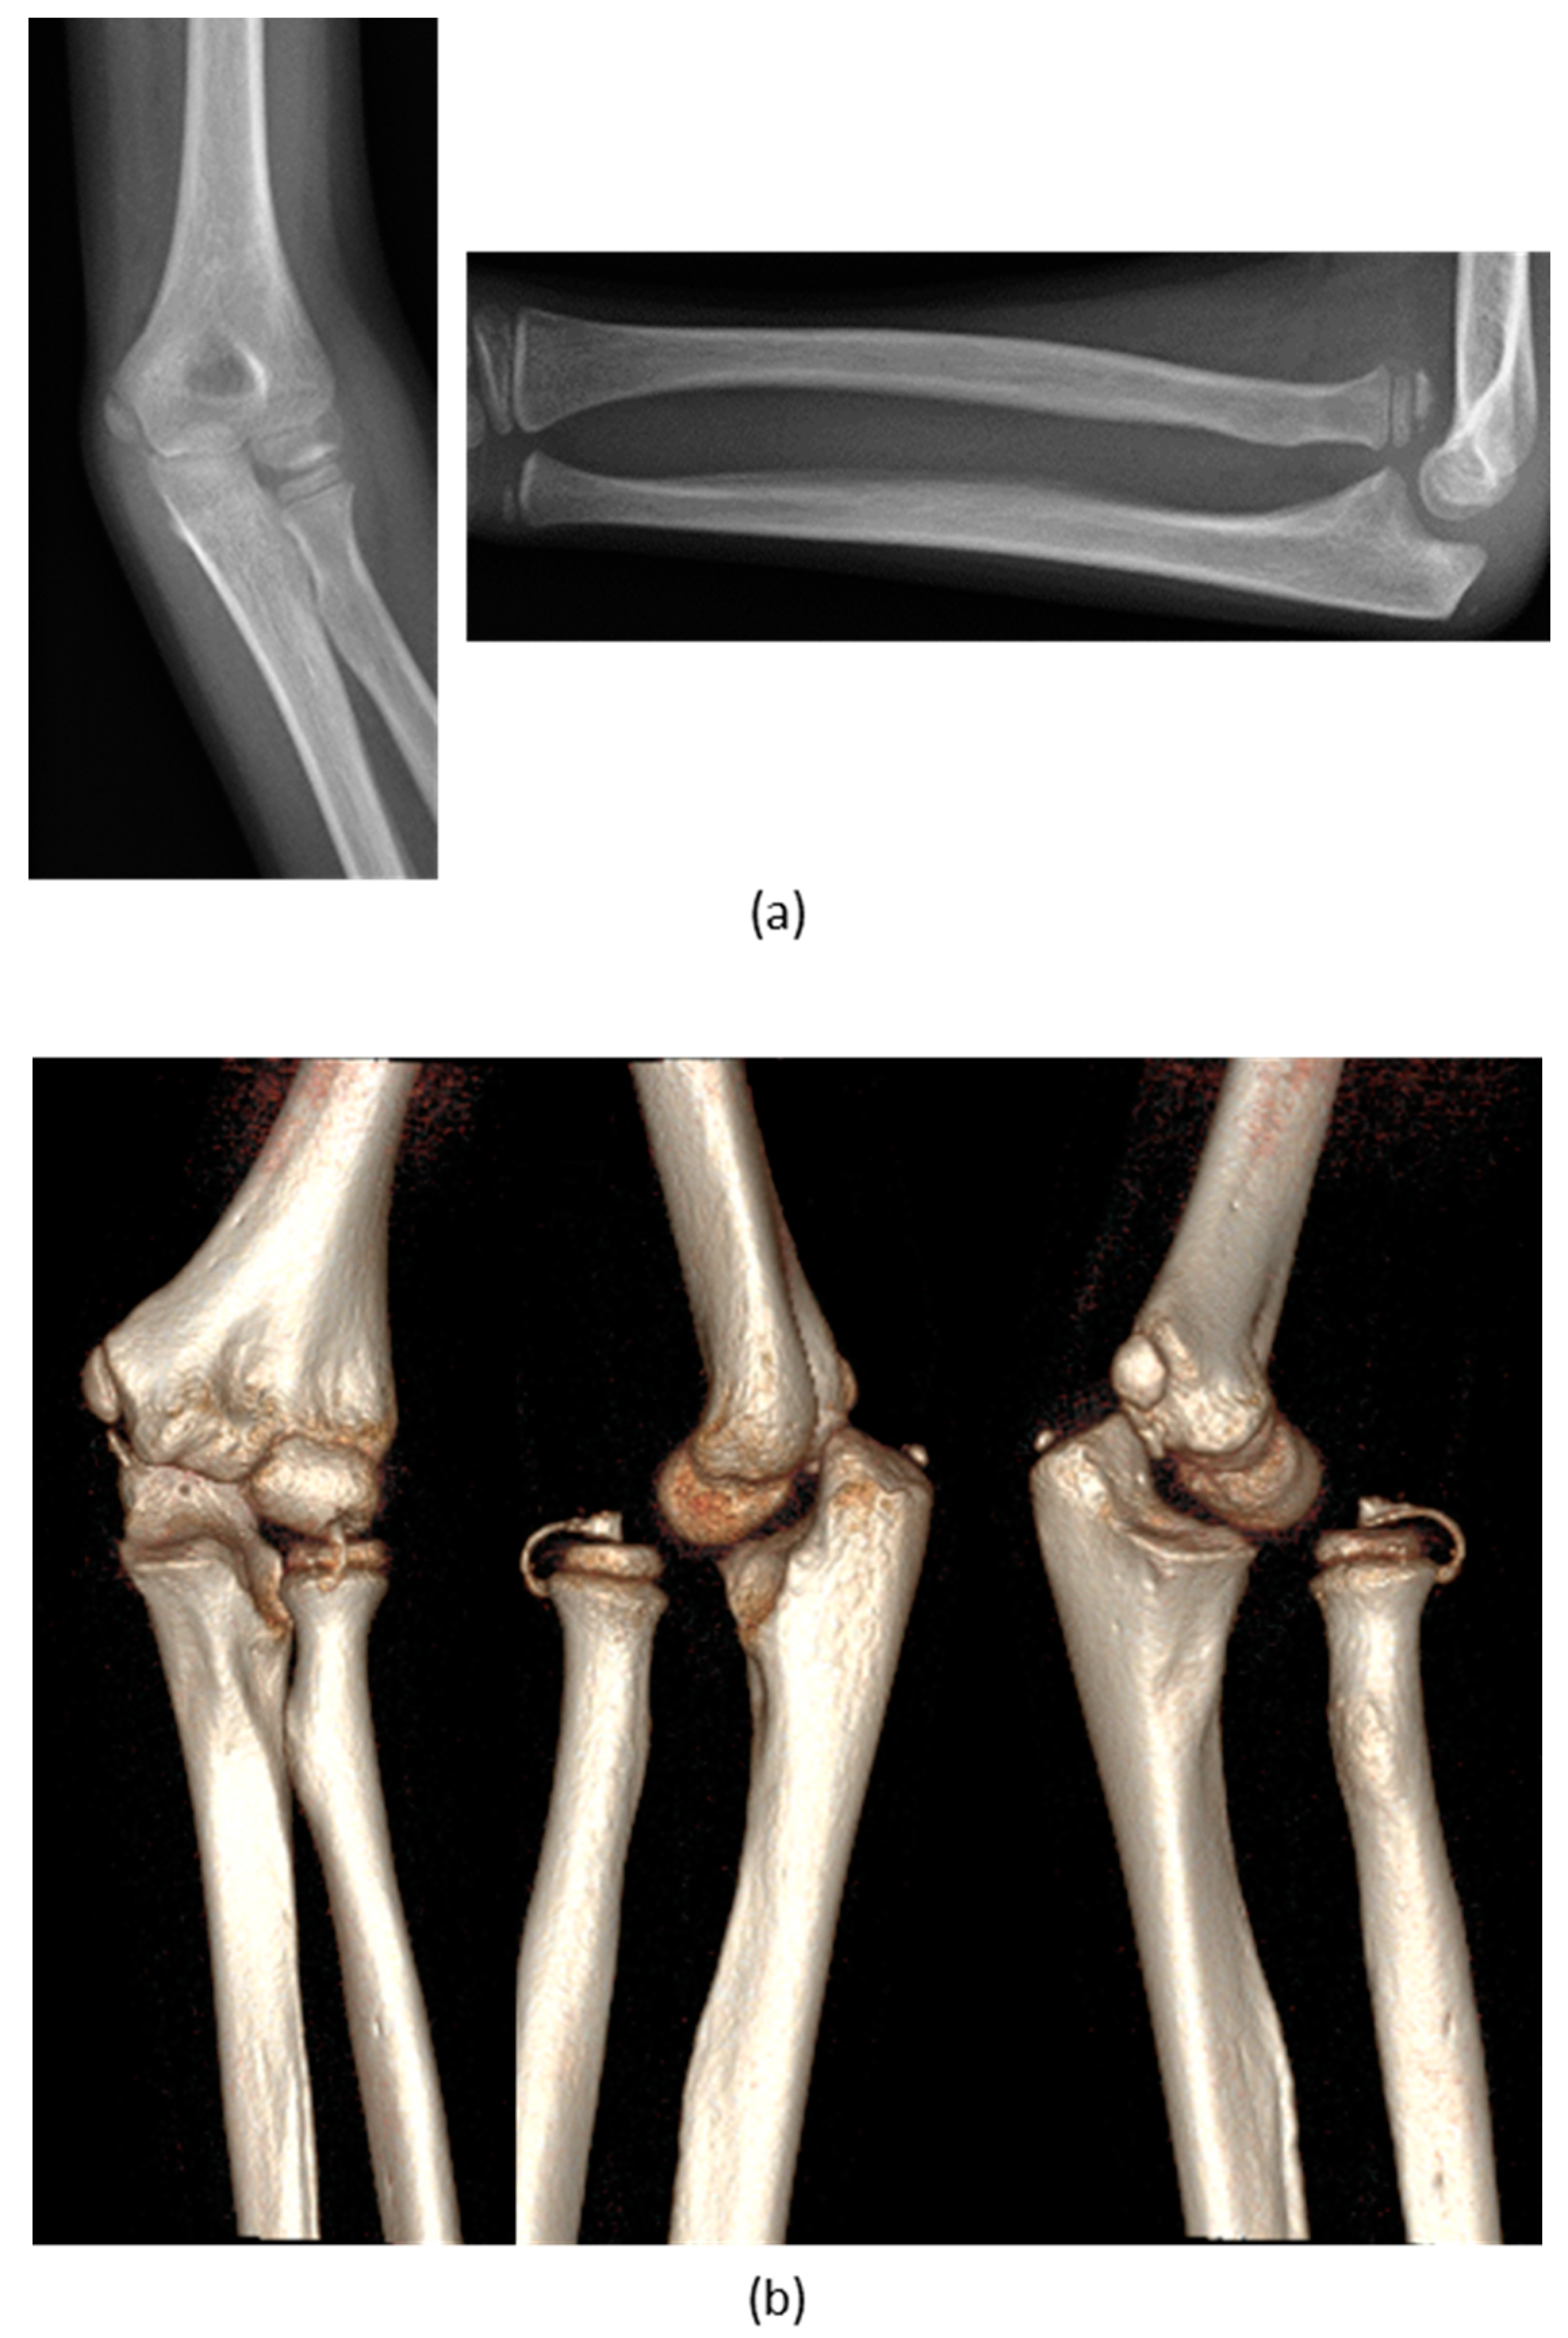

| 1 | F, 9 | Missed Monteggia Lesion | Post-traumatic | Proximal ulnar osteotomy stabilized with a 6-holes plate | None | Corrected |